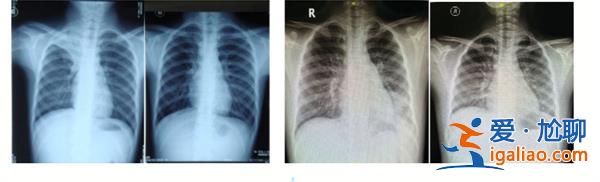

洗肺注意是支原體肺炎導(dǎo)致的病癥,男童需要洗肺才能治療。據(jù)了解這名男童家住在新鄭,最近因為持續(xù)高燒不退,便被父母帶著去了河南省胸科醫(yī)院,入院檢查后,發(fā)現(xiàn)男童是感染支原體肺炎,癥狀比較嚴重,且有加重的趨勢。在醫(yī)院快速辦理入住手續(xù)后,男童的病情得到了穩(wěn)定。住院以后,亮亮的高燒還在持續(xù),醫(yī)院便決定給他洗肺。亮亮的主治醫(yī)師在綜合考慮結(jié)果以后,決定對他進行肺泡灌洗。

洗肺是民間口頭的說法,在醫(yī)院被叫做支氣管肺泡灌洗術(shù),這是一種通過支氣管鏡進行微創(chuàng)的手術(shù),把支氣管的軟鏡通過口鼻,置入患者支氣管內(nèi),這能方便醫(yī)生直接觀看患者體內(nèi)的病變情況。利用醫(yī)學(xué)技術(shù)對肺泡進行灌洗后,把灌洗液送到其他部門檢測,能明確亮亮的病癥。